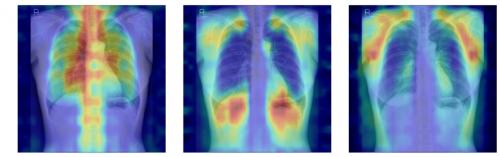

ÈäºÎX¼±¿¡¼­ ÆÄ¿îµ¥ÀÌ¼Ç ¸ðµ¨ÀÌ °ñ´Ù°øÁõ ÆÇµ¶À» À§ÇØ ÁÖ¸ñÇÑ ¿µ¿ªÀ» ½Ã°¢È­ÇÑ À̹ÌÁö.

AI´Â ÀÔ·ÂµÈ ÈäºÎ X¼±¿¡¼­ ôÃß¿Í ´Á°ñ °°Àº »À ±¸Á¶¸¦ Áß½ÉÀ¸·Î Ư¡À» ÃßÃâÇϰí, À̸¦ ±âÁ¸¿¡ ÇнÀµÈ ÆÐÅϰú ºñ±³ÇØ Á¤»ó(T-score ≥ -1.0), °ñ°¨¼ÒÁõ(-2.5 < T-score < -1.0), °ñ´Ù°øÁõ(T-score ≤ -2.5) Áß ¾î¶² »óÅÂ¿Í °¡Àå À¯»çÇÑÁö¸¦ ÆÇ´ÜÇÑ´Ù.

¿¬±¸ÆÀÀº ¿©±â¿¡ ´õÇØ AI°¡ ½ÇÁ¦·Î ¾î¶² »À¸¦ ±Ù°Å·Î »ï¾Æ ÆÇ´ÜÇÏ´ÂÁö±îÁö È®ÀÎÇÒ ¼ö ÀÖµµ·Ï ‘¼³¸í °¡´É¼º’ Æò°¡ ü°è¸¦ ¼³°èÇß´Ù. »À¸¦ ¸ðµÎ °¡¸° »óÅ¿¡¼­ ƯÁ¤ »À ºÎÀ§¸¦ Ãß°¡ÇØ ¼º´ÉÀÌ ¾ó¸¶³ª Çâ»óÇÏ´ÂÁö È®ÀÎÇÏ´Â ‘Â÷´Ü ºÐ¼® ¹æ½Ä(Δbone)’°ú Grad-CAMÀ¸·Î ³ªÅ¸³­ AIÀÇ ÁÖ¸ñ ¿µ¿ªÀÌ ½ÇÁ¦ »À À§Ä¡¿Í ¾ó¸¶³ª ÀÏÄ¡ÇÏ´ÂÁö¸¦ °è»êÇÏ´Â ‘À¯ÀǼº Áöµµ ¹æ½Ä(IoUbone)’À» ÅëÇØ, AI°¡ ÀÓ»óÀûÀ¸·Î Áß¿äÇÑ »À ±¸Á¶¸¦ ±Ù°Å·Î ÆÇ´ÜÇÏ´ÂÁö¸¦ Á¤·®ÀûÀ¸·Î °ËÁõÇß´Ù.

±× °á°ú, DINOv2 ¸ðµ¨¿¡ LoRA ¹æ½ÄÀ» Àû¿ëÇÑ ¸ðµ¨ÀÌ AUC 0.93(95% CI 0.92–0.94)·Î °¡Àå ³ôÀº ¿¹Ãø ¼º´ÉÀ» º¸¿´´Ù. ÀÌ ¸ðµ¨Àº »À ±¸Á¶ Ȱ¿ëµµ°¡ °¡Àå ³ô°í, ÁÖ¸ñ ¿µ¿ªÀÇ Å¸´ç¼º¿¡¼­µµ ¿ì¼öÇØ, ¿¹Ãø·Â°ú ¼³¸í °¡´É¼ºÀÌ ±ÕÇü ÀÖ°Ô È®º¸µÈ ÃÖÀû ¸ðµ¨·Î Æò°¡µÆ´Ù.